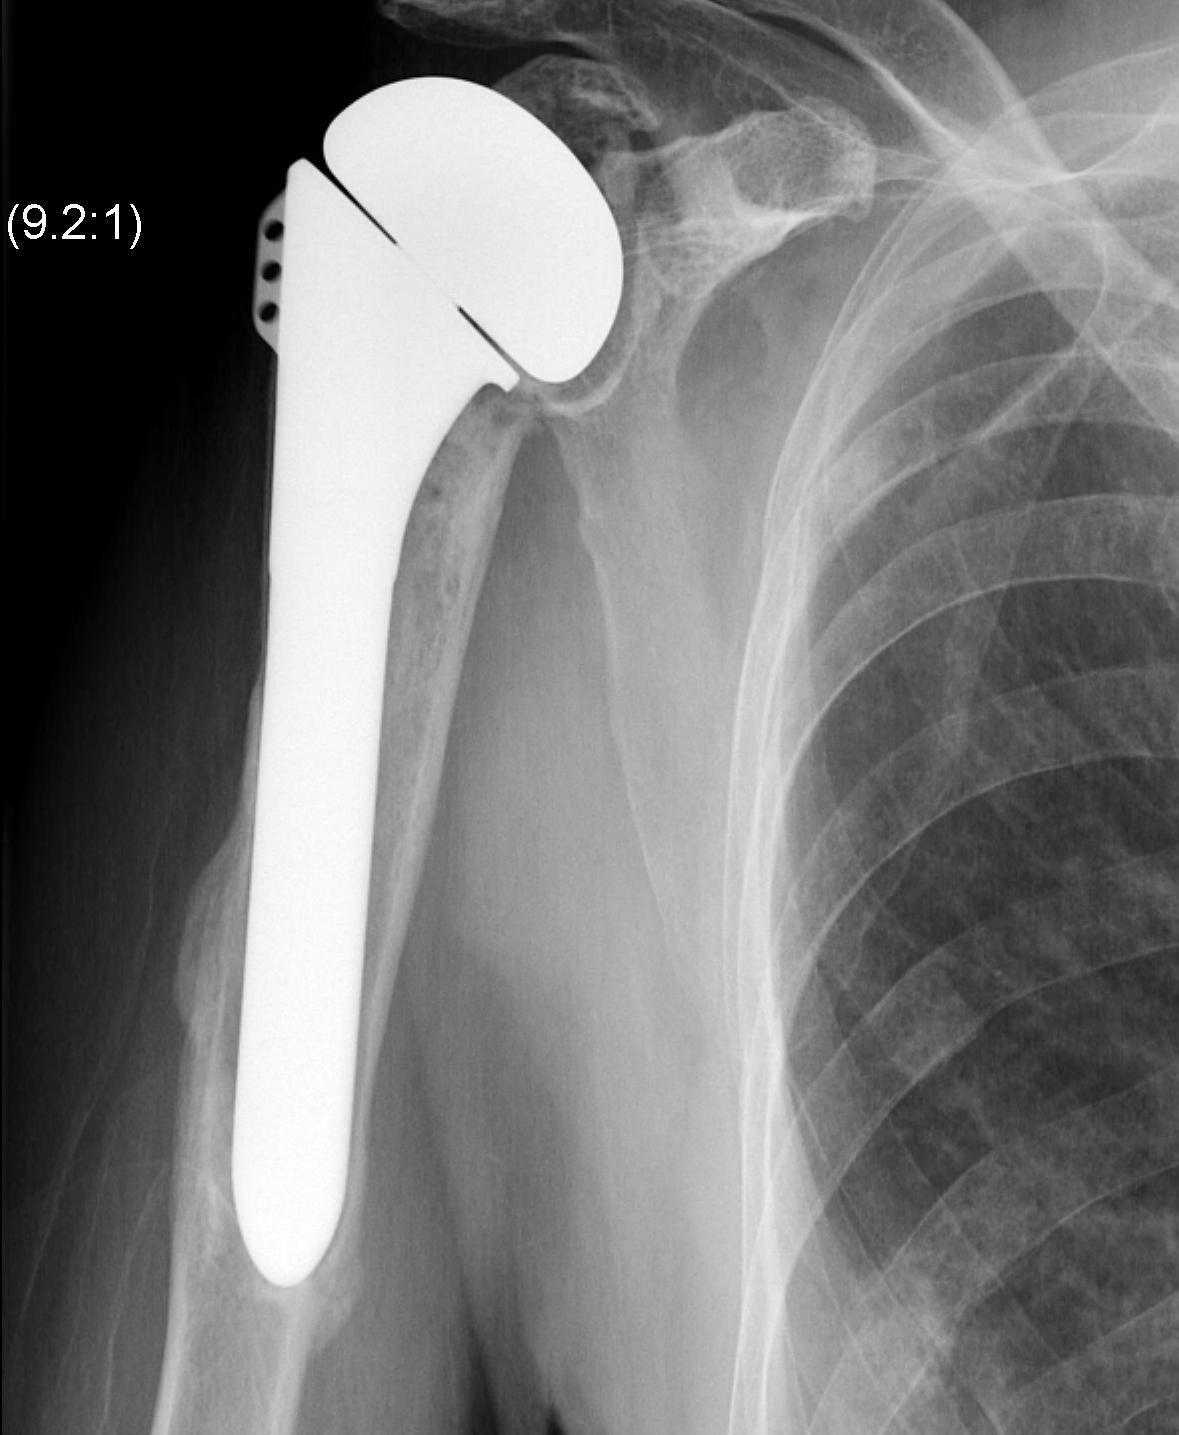

Superior migration of humeral head on xray

Shoulder Hemiarthroplasty Rotator Cuff FailureTSR Superior EscapeaTSA failed cuffTSR Failed Rotator CUff

Overstuffed aTSARevision to revTSA